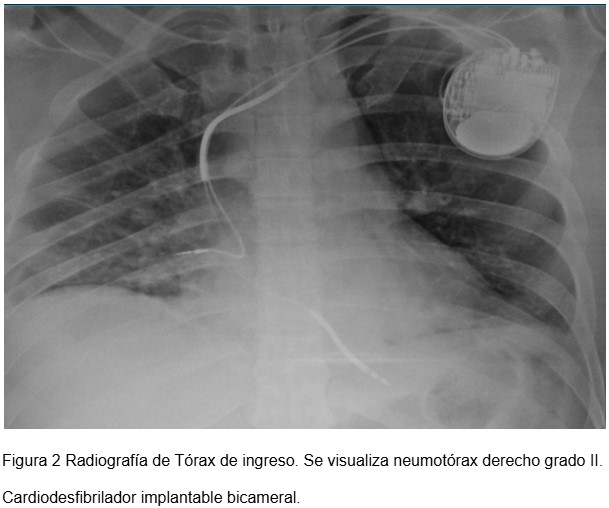

Introducción: Las indicaciones de implante de cardio desfibriladores en la pobl...